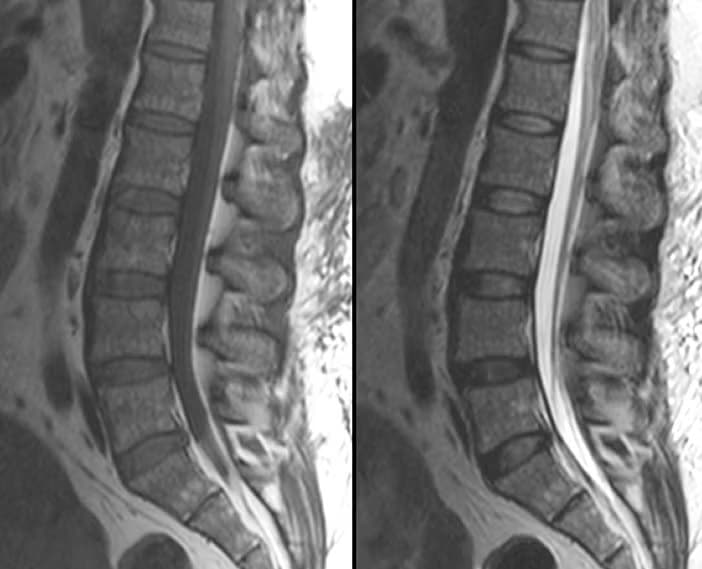

Discover the cause of your back pain with Lumbar MRI! Fast and reliable MRI imaging service with expert radiologists. Click for medical imaging center options.

Discover the cause of your neck pain with Cervical MRI! Fast and reliable MRI imaging service with expert radiologists. Click for medical imaging center advantages!